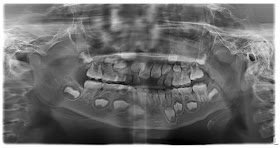

做媽媽的我當然想知道昕昕牙科全而情況,加上牙齒姐姐都明白我的擔憂,所以安排昕昕的牙齒照X光,價錢係$400,能夠全部牙睇曬收呢個價錢真係好過之前俾$120照幾隻牙仔~~~

依家的牙齒X光片係可以電腦輸出,檢查後數天可以電郵收到,昕昕在照X光時有少少郁,所以部份位置矇咗D,好在冇影響我們睇佢的情況~~~

牙醫姐姐話昕昕的恆齒大都已經在準備,門牙沒有牙腳紮根,所以不用擔心門牙唔會出來,牙醫姐姐仲安排昕昕兩個月後再檢查進度~~~

牙醫姐姐話昕昕的十四歲齒也在裡面,諗起我自己在17歲就出了智慧齒,莫非昕昕似我會早出大牙o(*≧▽≦)ツ